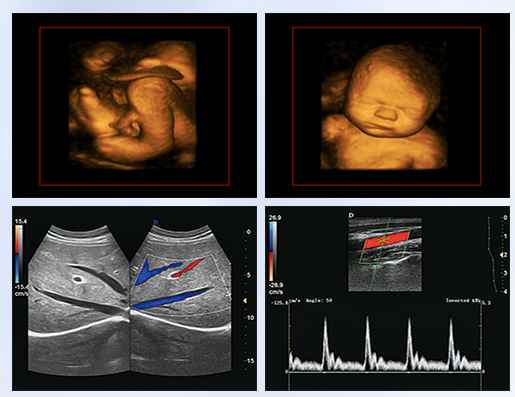

超聲學(xué)科的發(fā)展史,猶如一卷悠遠(yuǎn)綿長(zhǎng)的畫(huà)冊(cè)。從黑白B超機(jī)到彩超機(jī),從一維、二維向三維立體動(dòng)態(tài),從推車(chē)式B超機(jī)到便攜式彩超機(jī),從觀察人體解剖學(xué)到分析人體組織內(nèi)細(xì)微結(jié)構(gòu)和功能。隨著科學(xué)技術(shù)的不斷發(fā)展,B超機(jī)功能也越來(lái)越方便強(qiáng)大。

超聲作為一門(mén)醫(yī)、理、工相結(jié)合的學(xué)科,涵蓋超聲診斷、超聲治療和超聲工程技術(shù)等門(mén)類(lèi),其在臨床診斷和治療中發(fā)揮著日益重要的作用。B超機(jī)借助各種超聲探頭,以精湛的技術(shù)和嚴(yán)謹(jǐn)?shù)膽B(tài)度掃描著人體臟器內(nèi)的細(xì)微病變,給臨床提供準(zhǔn)確而快捷的檢查報(bào)告,在影影綽綽間,發(fā)現(xiàn)病魔的蛛絲馬跡中,用“金睛火眼”挽救患者性命……超聲的每一幅圖像,都是靠超聲醫(yī)生親自探查并采集的,每一個(gè)患者,至少都有10張以上的圖像存儲(chǔ),對(duì)于比較復(fù)雜的病例,有幾十甚至上百?gòu)垺6宜械膱D像,都需要超聲醫(yī)生在邊探查的時(shí)候,邊思考分析。這,是一個(gè)真正手腦并用的工作。